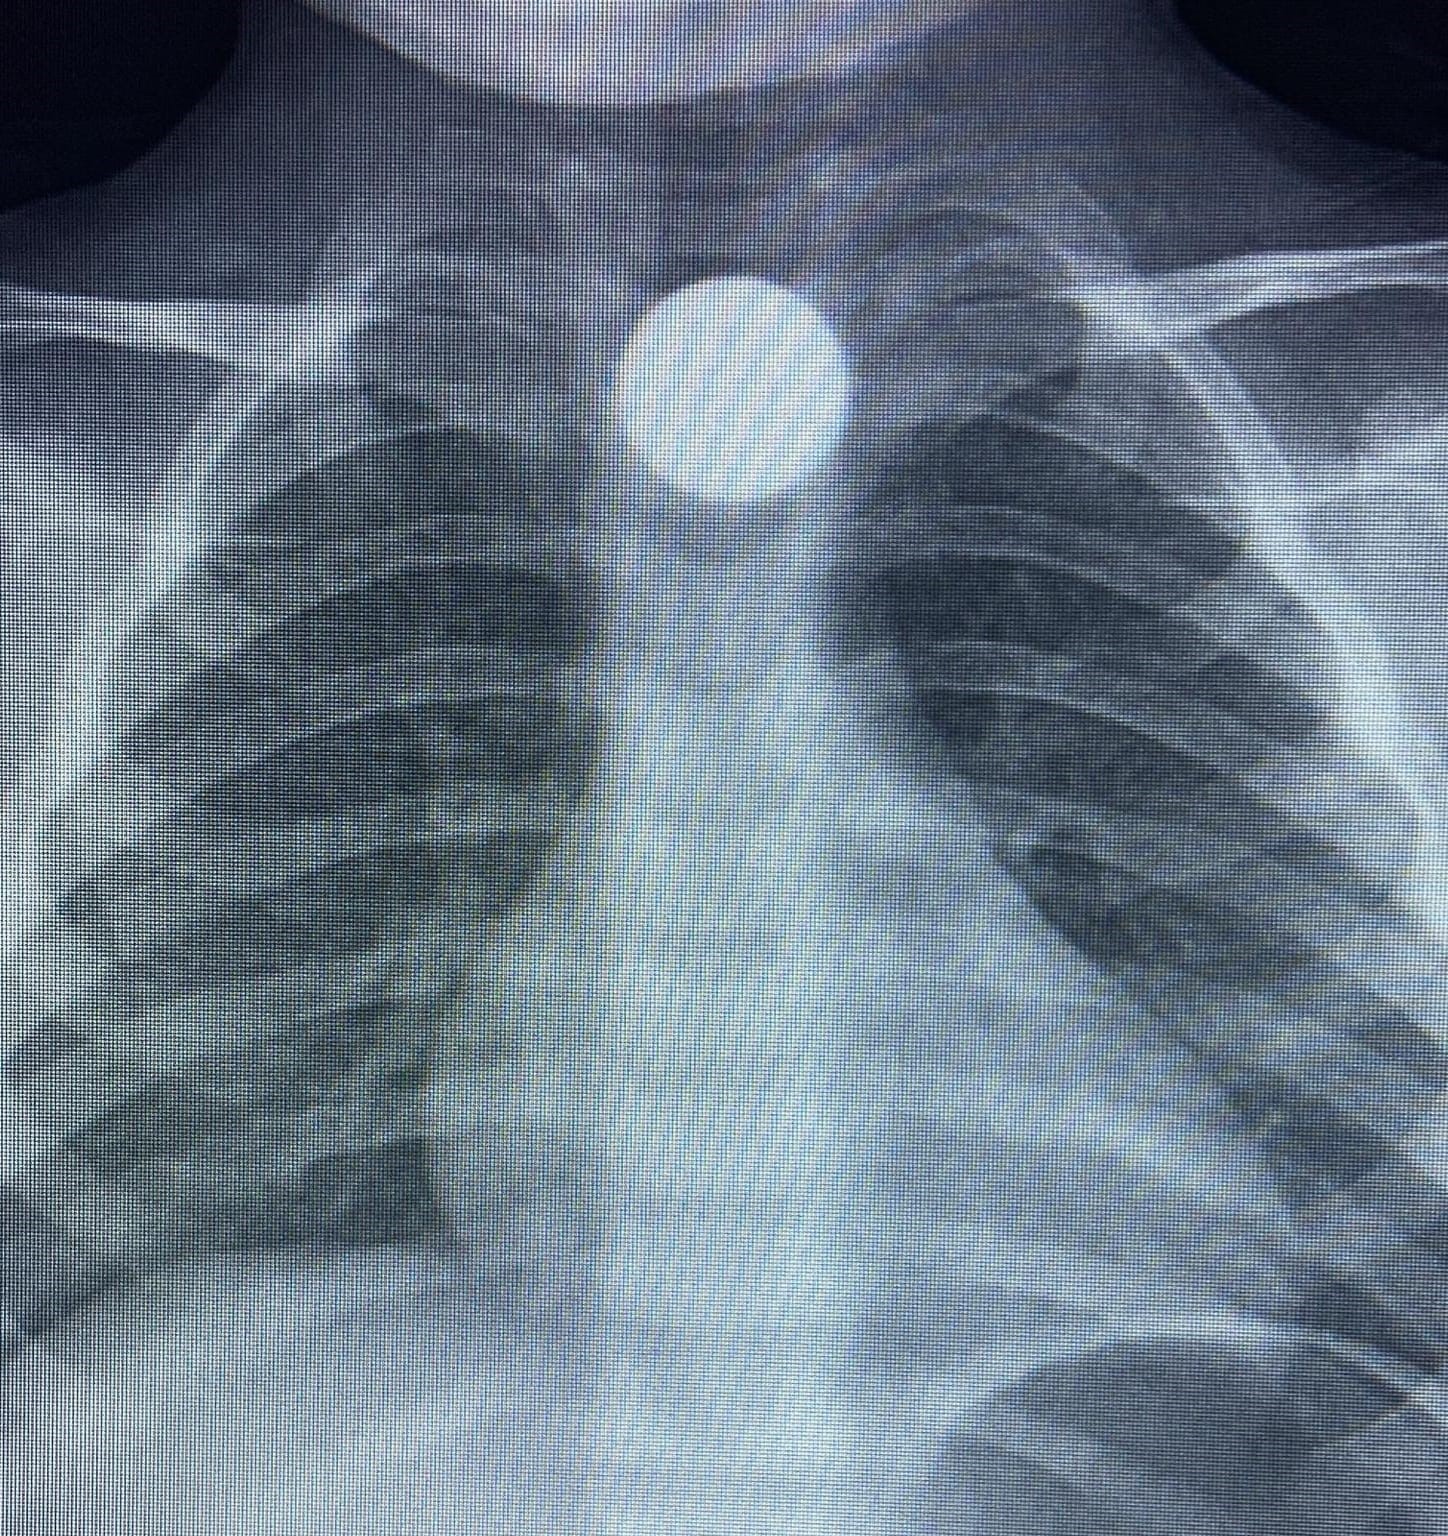

Yapılan tetkiklerde yemek borusunda takılı kalan madeni para görüldü. Çocuk ilk tedavinin ardından ambulansla Bursa Yüksek İhtisas Eğitim Ve Araştırma Hastanesi’ne sevk edildi.